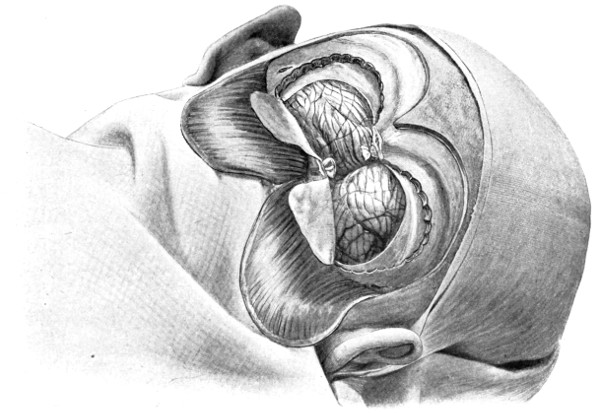

Fig. 19. Third Stage in the Formation of an Osteoplastic Flap. The dural flap turned down and the brain exposed. Note the relation of the scalp, bone, and dural incisions to one another.

To lift up the osteoplastic flap, a stout elevator or spatula is introduced beneath the bone at its upper part, leverage applied, and, as soon as sufficient elevation has been attained, the dura mater carefully separated from the whole of the under aspect of the flap. The flap is then grasped at its upper part with both hands and, with a quick but forcible jerk, broken across at its base, the assistant at the same time aiding the correct linear fracture of the bone by a flat spatula applied to the outer aspect of the base of the flap. Insomuch as the flap is most usually framed in the parieto-temporal region—for the exposure of the motor area—the base of the flap, being formed from the squamous portion of the temporal bone, is comparatively weak. Fracture is then readily obtained. Under other circumstances the base may be sufficiently weakened by the application of the de Vilbiss forceps or by the use of the Gigli saw.

The bone-flap is thrown back and enveloped in gauze. Its basal region is examined for a possible injury to meningeal vessels. In the event of such complications the bleeding vessel is clipped, ligatured, or underrun. Possibly some branch of the anterior division of the middle meningeal artery, running in an osseous canal, may require to be controlled by foraminal occlusion—with a wooden match, bone peg, cotton-wool, or aseptic wax.